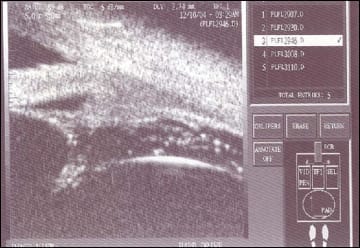

Figure 1. UBM image (top) shows a narrow hypoechoeic slit (black arrow) at the termination of which arises a membrane coursing posteriorly (white arrow). The latter is the commencement of the retinal detachment from the ora serrata. A UBM montage (bottom) shows a membrane attached at the presumed ora and coursing posteriorly in a patient with retinal detachment before surgical intervention.

The region of the ora serrata was characterized on UBM by the disappearance of a narrow hypoechoeic slit seen in all cases. This possibly represented the supraciliary space. Detachment of the retina could be deciphered by detection of a membrane attached to the presumed ora serrata and passing posteriorly with a downward slope (Figures 1 and 2). In the two patients with silicone oil-filled eyes and opaque media due to cataracts, intraoperative confirmation of a peripheral retinal detachment was obtained in one patient and its absence in the other. Disinsertion of the retina from the ora serrata (retinal dialysis) in a patient with posttraumatic retinal detachment with dialysis was also documented (Figure 3).